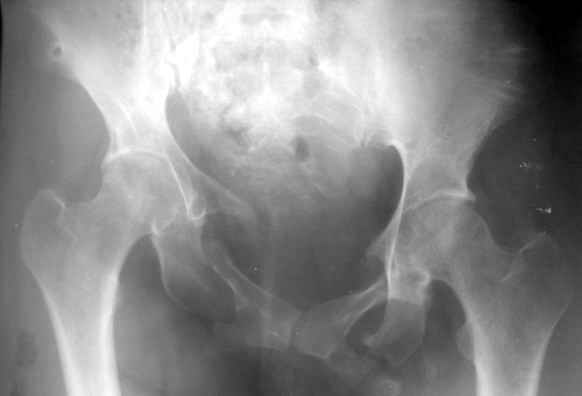

Вопрос Уральскому Пельвиоцентру: через год после травмы, довольно симпатичная женщина, болей нет, только ходит призрамывая на правую ногу и сидит криво, мышечная ассиметрия практически не выражена, хотя слабость справа есть. Легко компенсируется подкладкой стельки 1,5 см с выраженным клиническим эффектом. Посылаю снимки с вопросом - можно ли устранить деформацию в Вашем аппарате, если можно - то поподробнее. Снимки с разницей во времени почти 1 год. Жду ответа как соловей лета. ЛАФ.

Привет! Случай типичный при такой травме, когда накладывают переднюю раму аппарата, но репозиции не достигают и игнорируют повреждение задних отделов. Интересно узнать всю историю поподробнее, где и как лечилась, сроки, была ли информация у больной, что ей можно было помочь гораздо раньше и с большим эффектом.

На счет жалоб: к году полутора при этом повреждении больные приспосабливаются к новым условиям и активно предъявляют жалобы, как правило, только на боли, с которыми они смирились и хромоту. Перелом боковой массы крестца или срастается или образует достаточно спаек для стабилизации повреждения в отличие от чистых разрывов КП сочленения.

Однако при расспросе картина становится более ясной, т.к. выявляются ограничения в ходьбе, сидении, лежании и способности к труду. Мы пользуемся универсальными шкалами, хорошо бы узнать ее баллы по Majeed. Для уточнения диагноза и степени сращения необходимы дополнительные проекции inlet, outlet и обязательно КТ таза с шагом 0,5мм. Не плохо было бы и общий вид узреть - фас, сзади и стоя на одной ноге.

Объем хирургического пособия зависит от этих данных.

Привожу пример лечения больного с 7 месячной деформацией. Отеотомии - аппарат - внутренняя фиксация.

Рентгенограммы до и через месяц после окончательной стабилизации. Потом поищу более поздние снимки.